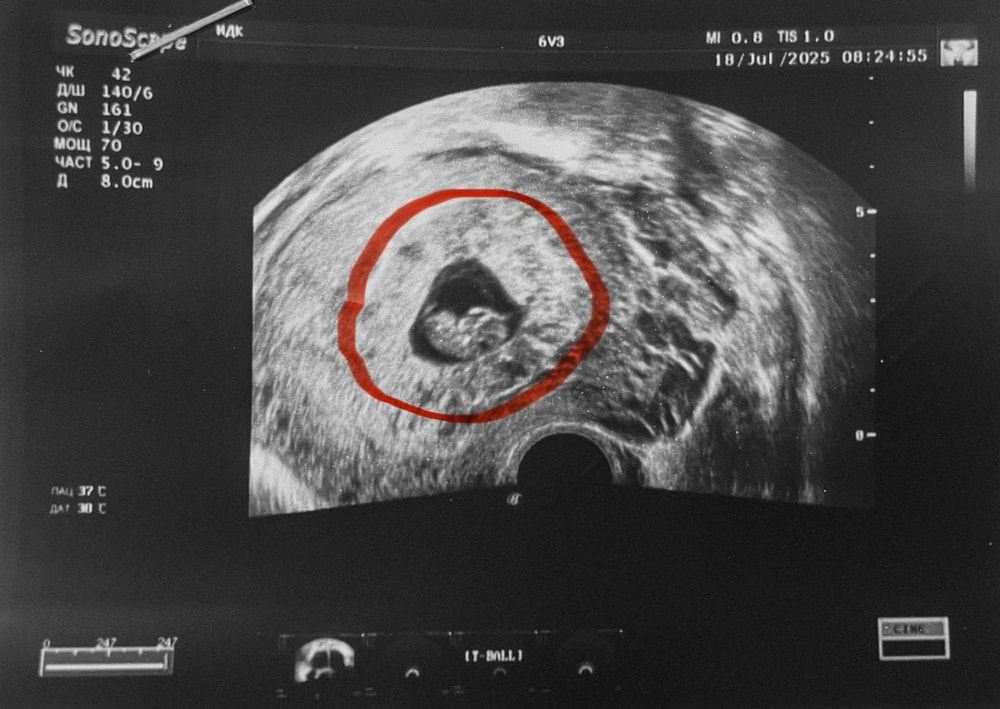

Оксана, спасибо большое, я на это надеюсь! Мне врач сказала, что само ПЯ большое, нормального размера (я обвела границы красным), но хорион еще не облысел и поэтому занимает большую площадь ПЯ. Когда начнется процесс "облысения", тогда и места эмбриону будет больше. Не знаю, насколько это правда.

Ирина ツ, вот сказали. Предыдущий пост у меня. Циркулярное расположение хориона или кольцевидный хорион. Свободного места в ПЯ всего 25 мм, все плодное яйцо не измеряли.

Алина, кольцевидный хорион это норма для срока,а вот пя маленькое для такого эмбриона,сама сталкивалась, поэтому обращаю внимание на размеры пя по соотношению к ктр,это не очень хорошо,мало места там и часто заканчивается печально,но я не утверждаю что 100% может вам и померяли неправильно его,хотя по фото места мало